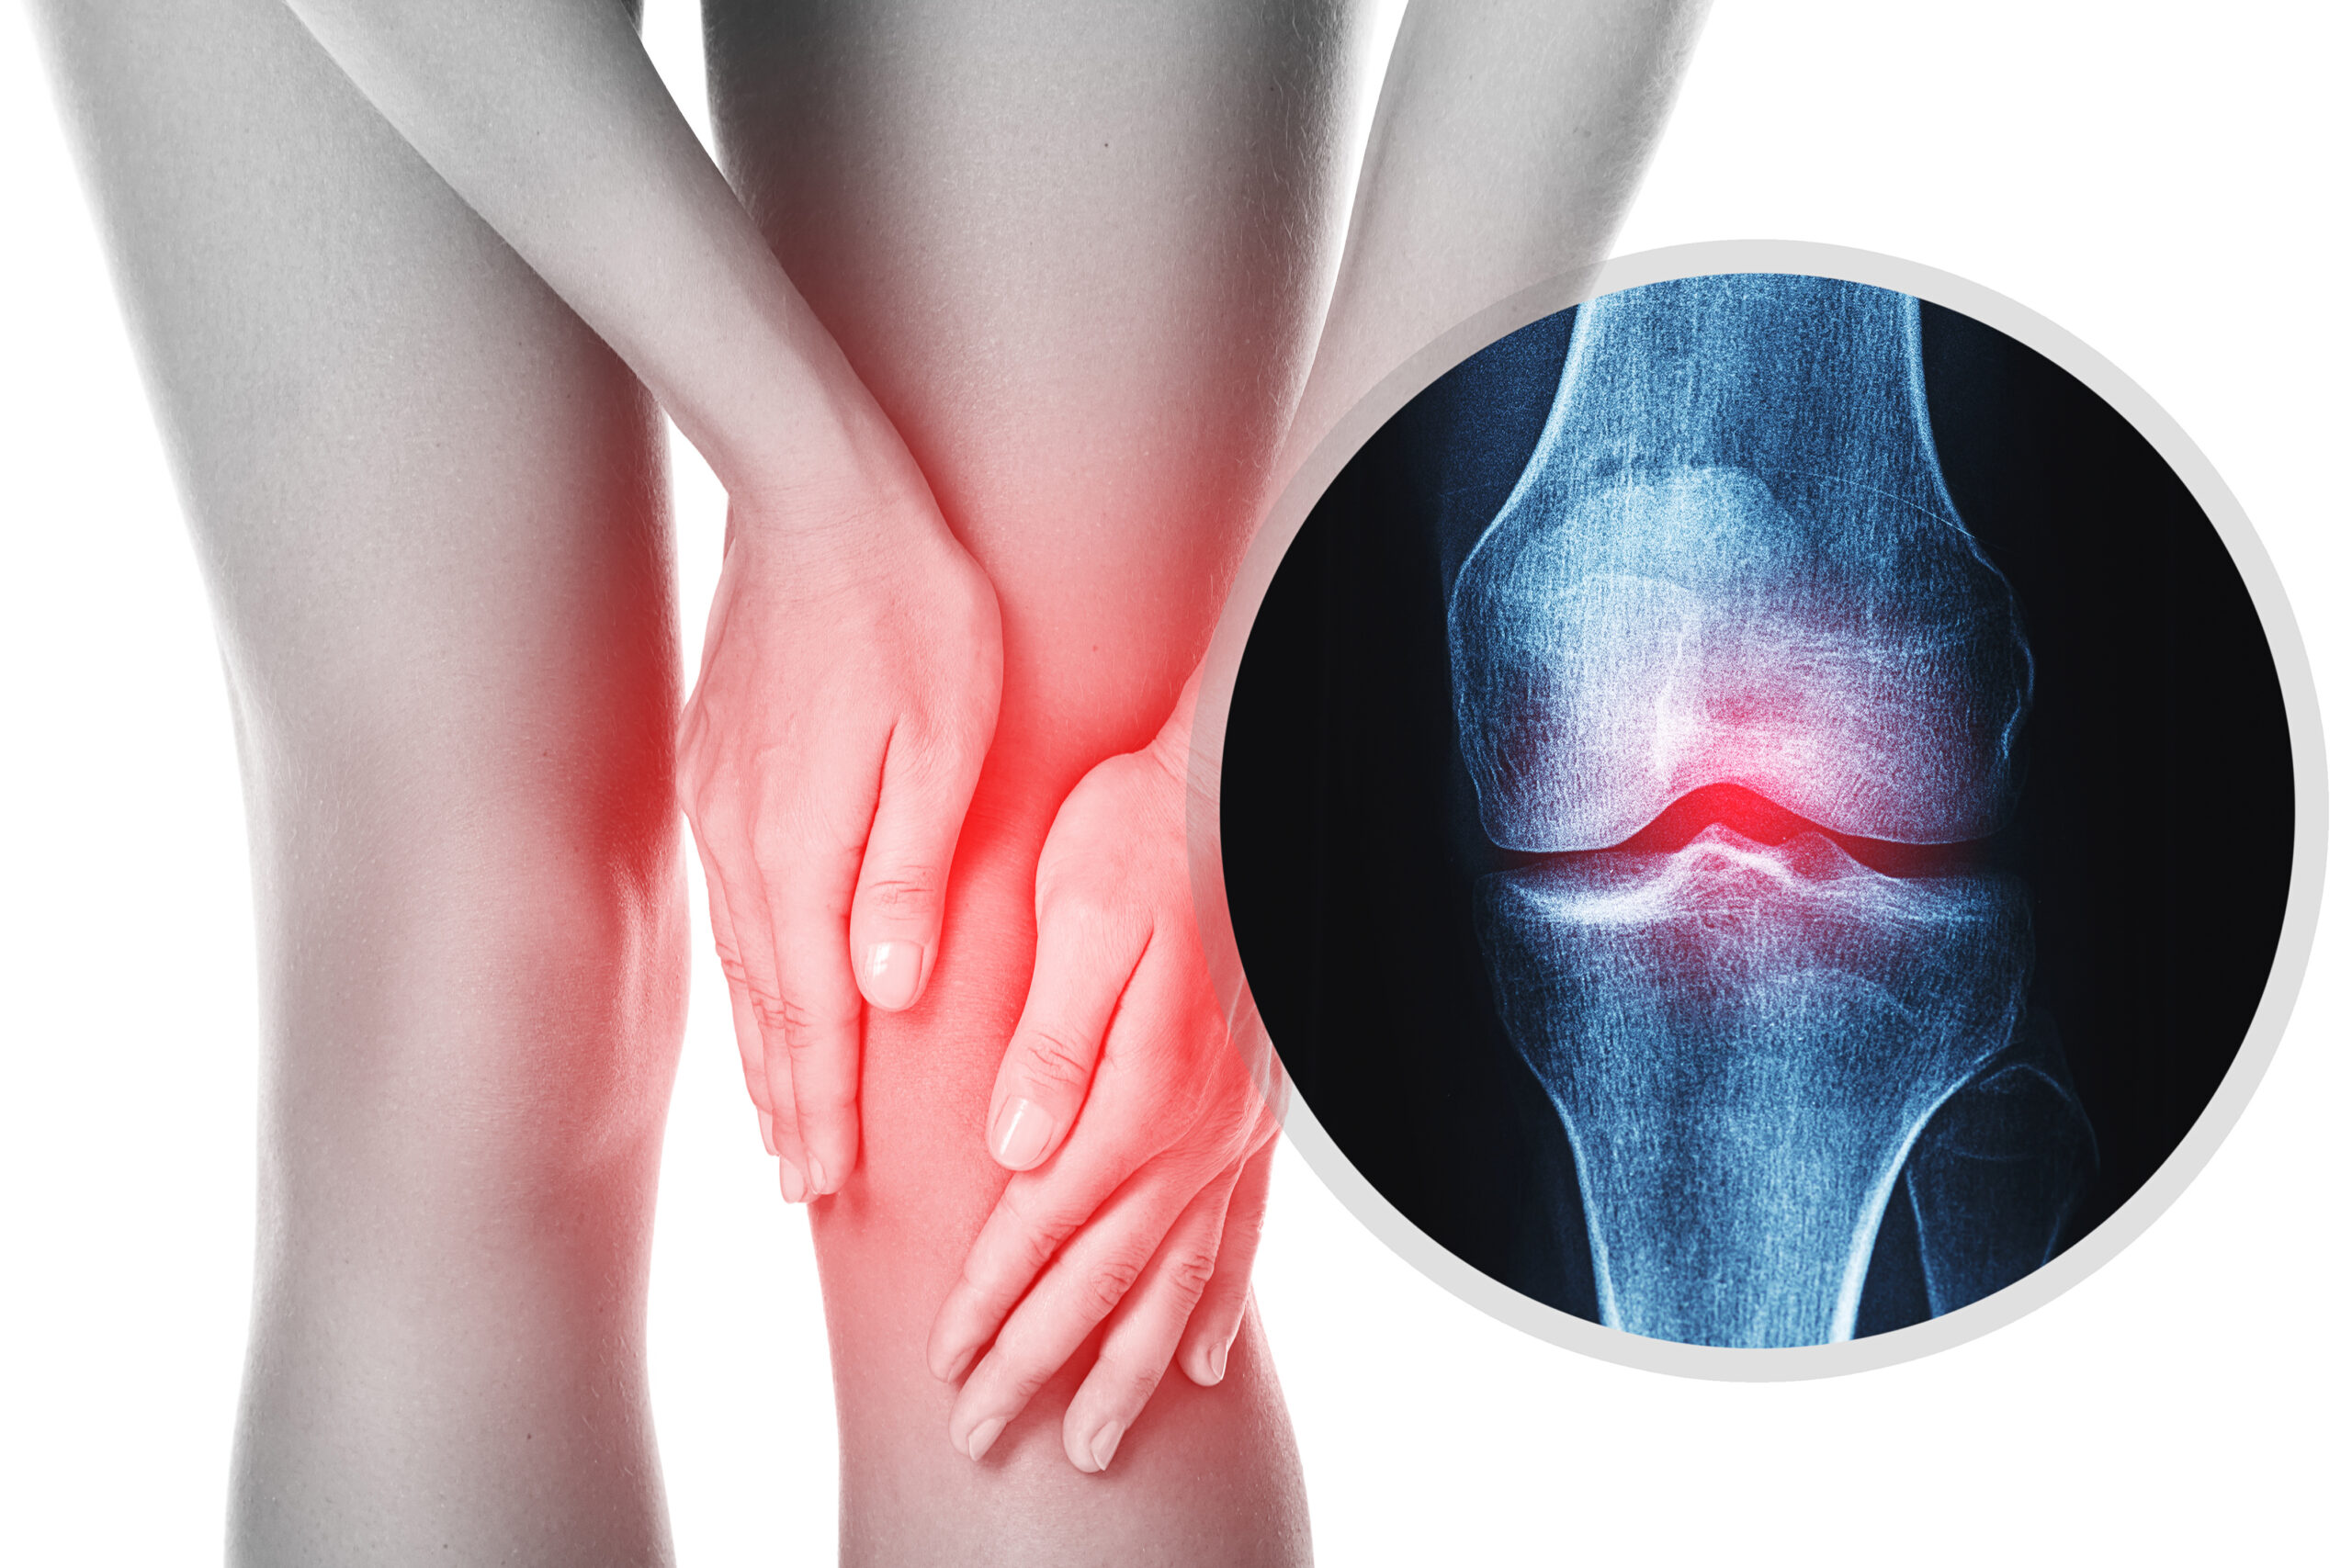

LOOKING FOR A LASTING SOLUTION TO ARTHRITIS, PARTIAL STROKE, RHEUMATISM AND ALL OTHERS BODY PAINS?

DONT MAKE UP YOUR MIND TO LIVE WITH ARTHRITIS PAINS FOREVER...

- Do you suffer from severe joints pain especially in your legs and lower back?

- Do you find it hard walking long distances because of knee pains?

- Does your knee ache with sharp pains that feel as if a sharp needle was placed inside?

- Have you had serious waist pain that just refuses to go again even after trying different pills?

- I am here to help you get rid of deadly arthritis and all others body joint pains.

NATURAL CURE TO ARTHRITIS, RHEUMATISM,OSTEPOROSIS & SPNDYLOSIS E.G PAINS IN JOINT, WAIST, KNEES, SHOULDER, WRIST, LEG E.T.C